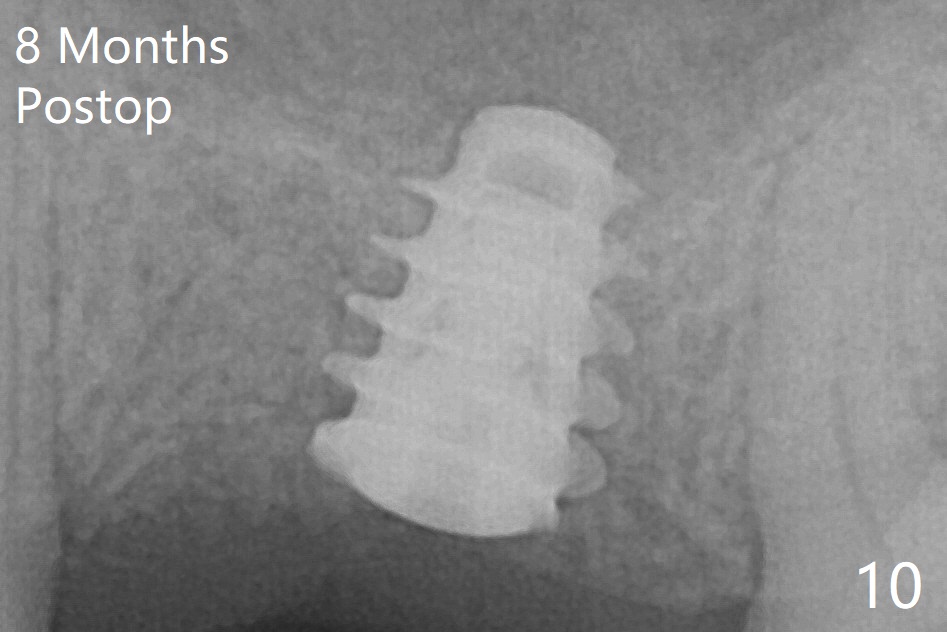

The implant is mobile 4 months postop (Fig.6).  A 6x2 mm healing abutment is placed next.  Although the implant remains mobile 6 months postop, the bone seems to have become denser around the implant (Fig.7-9).  A healing screw is placed.  When the bone height is limited (<7 mm), place a larger implant (>5.5 mm).  The implant seems to have osteointegrated 8 months postop (Fig.10).  Impression is taken following placing a 6.5x4(3) mm abutment.  The patient reports pain after cementation, which is less when the abutment screw is loose (9.5 months postop, 2 weeks post cementation).  CBCT taken after placement of a healing screw apparently shows loose bone mesial and distal to the implant (Fig.11 *).  The implant trajectory is less favorable.  It seems necessary to change to a large implant with more sold threads (Fig.12).